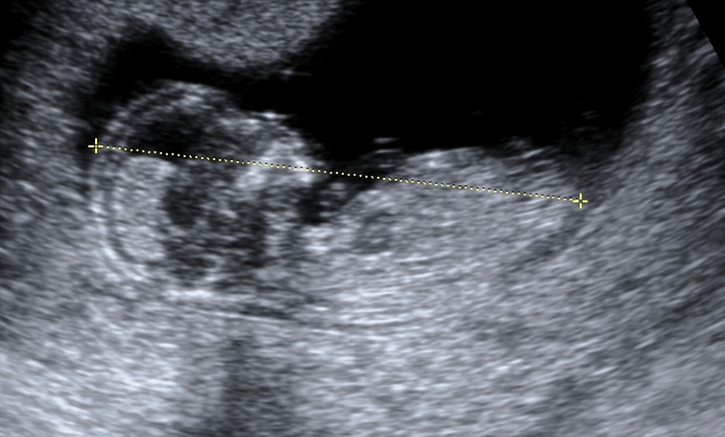

Baş-popo uzunluğu, bebeğinizin başının üst kısmından poposuna kadar olan mesafeyi ifade eder. Genellikle hamileliğin 6. haftasından itibaren yapılan bu ölçüm, 14. haftaya kadar bebeğinizin gelişimini izlemek için kullanılır. Bu dönemde bebek henüz bacaklarını tamamen uzatmadığı için baştan popoya kadar olan mesafe en doğru şekilde bebeğin büyümesini gösterir. Ölçüm, milimetre cinsinden yapılır ve bebeğin yaklaşık kaç haftalık olduğunu hesaplamada önemli bir rol oynar.

Gebeliğin ilk üç aylık döneminde yapılan ultrason kontrollerinde baş-popo uzunluğu ölçümü düzenli olarak yapılır. 6-14 hafta arasında, bebeğin boyu ve kilosu hakkında bilgi sahibi olmak için bu yöntem idealdir. Bu ölçüm sayesinde doktorunuz, gebeliğinizin doğru haftada olup olmadığını doğrular ve bebeğinizin gelişiminde herhangi bir sorun olup olmadığını erken dönemde tespit edebilir.